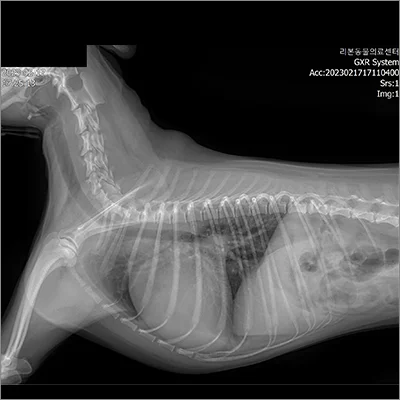

PDA 전

PDA 후

폐엽절제 전

폐엽절제 후